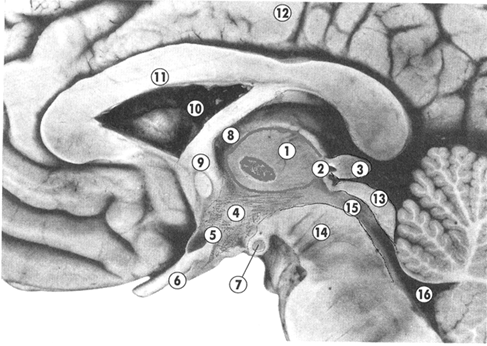

Рис.1. Фотография сагиттального среза промежуточного мозга

1 – таламус; 2 – эпиталамус; 3 – эпифиз; 4 – гипоталамус; 5 – воронка серого бугра; 6 – зрительный перекрест; 7 – сосцевидные тела; 8 – межжелудочковое отверстие; 9 – свод; 10 –боковой желудочек; 11 – мозолистое тело; 12 – полушария конечного мозга; 13 – пластинка четверохолмия; 14 – ножка мозга; 15 – водопровод мозга; 16 – IV желудочек